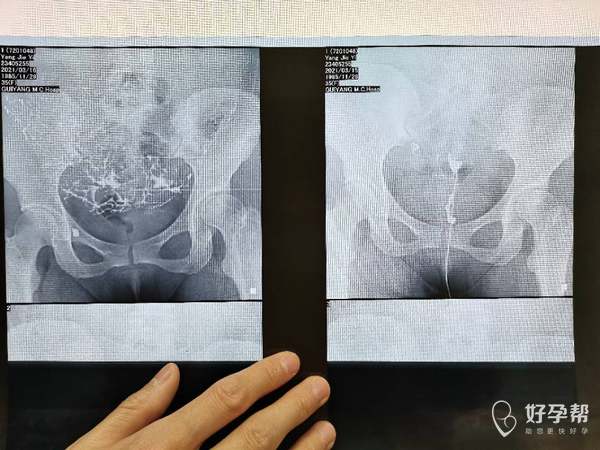

请问造影片子上能看出是输卵管哪里堵塞吗做腹腔

从片子看你这个是输卵管远端阻塞,做宫腹腔镜联合手术效果比较好